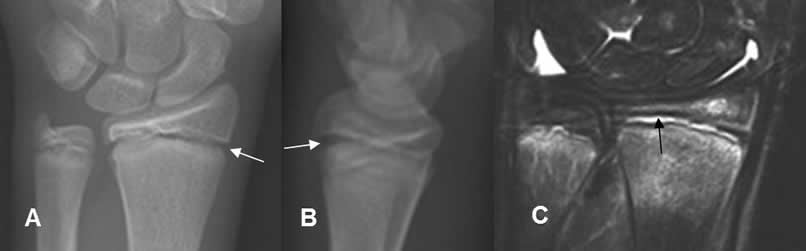

Fig 70. Salter tipo I.

A: Rx AP y B: Rx lateral. Aumento del espacio metafisoepifisiario radial.

C: RM coronal en STIR. Edema óseo del radio y cúbito distal, por contusión. Líquido sobre la placa de crecimiento, por deslizamiento epifisiario tipo I. (Flecha negra).